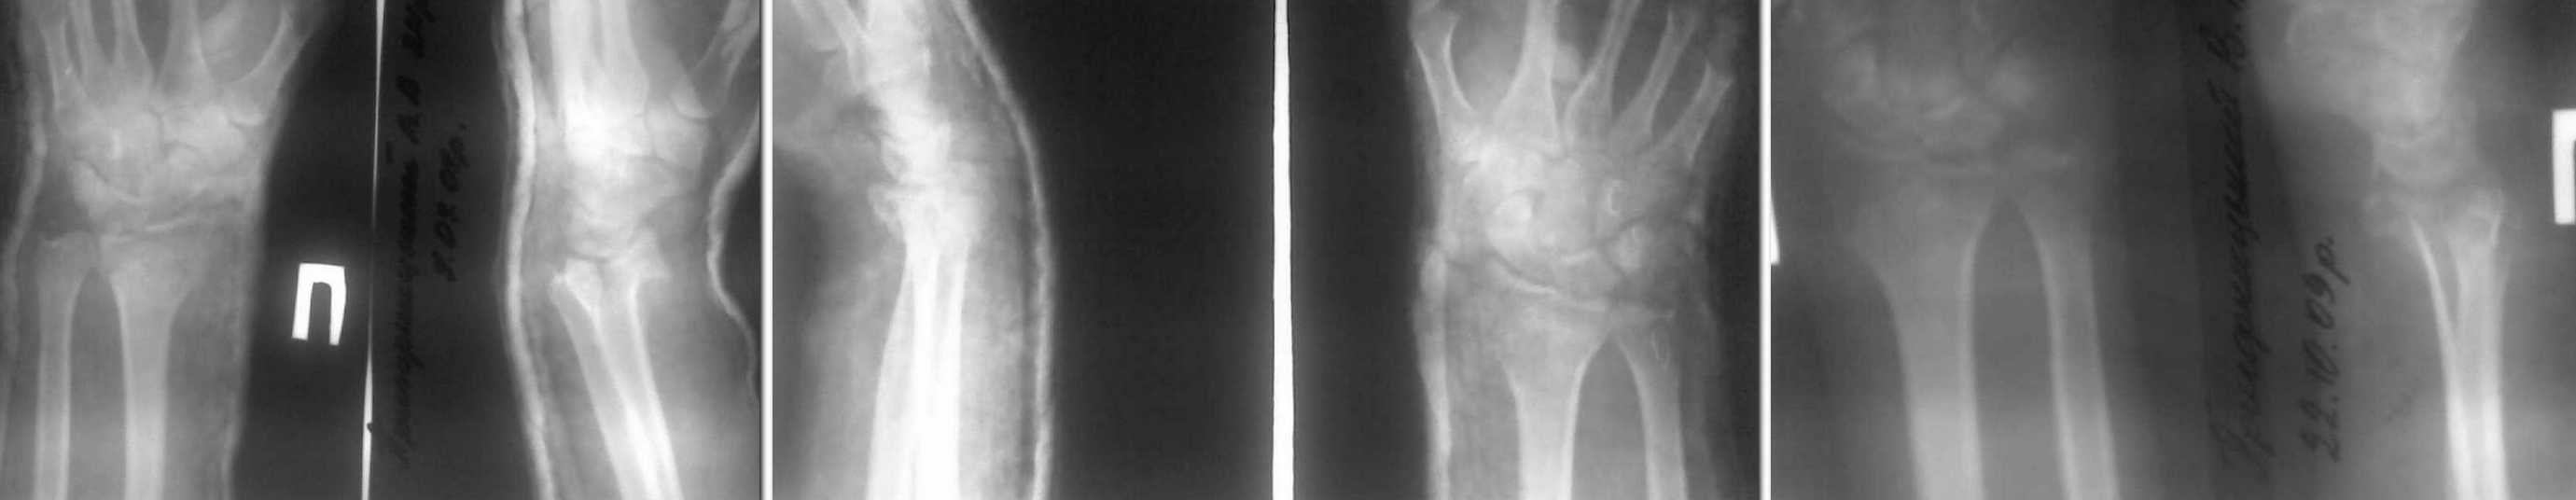

Здравствуйте, уважаемые коллеги.Хотим услышать Ваше мнение по поводу лечения пациента 24 лет с диагнозом неправильно консолидирываный внутрисуставный перелом дистального метаэпифиза правой лучевой кости. Травма 3 мес назад. Была выполнена закрытая репозиция, гипсовая иммобилизация. 2 мес. назад гипсовая повязка снята, и больной начал разрабатывать движения. Сейчас жалобы на боли в лучезапястном суставе, появляющиеся после физической нагрузки, особенно ограничено и болезненно тыльное сгибание, остальные движения ограничены в меньшей степени, слегка болезненны в крайних положениях. Неврологических нарушений клинически нет. Пациент военнослужащий, физического труда.Мы рассматриваем такие варианты: 1. Продолжить разработку движений с физметодами2. оперативное лечение с восстановлением анатомических соотношений в суставе.

Уважаемый Евгений, возможно, полезной для предоперационного планирования может оказаться Ргр здорового лучезапястного сустава, особенно в том случае, если данная операция не является рутинной для Вас. Тогда, отталкиваясь от Ргр здорового сустава, как от идеального шаблона, Вы сможете максимально аргументировано составить предоперационный план, в том числе и определиться с уровнем остеотомии. Так же нашёл у себя в архиве более - менее похожий случай, он во вложенном файле, может что-то окажется полезным для Вас. Пациентка 26 лет, упала с велосипеда. Лечилась консервативно. Обратилась к нам через 3 мес. Ргр на 1ом слайде. При этом достаточно хорошо видна и импрессия хряща. Выполнена остеотомия, зона её открыта, как книга и с помощью импактора возвращены на место вдавленные участки суставной поверхности, при этом суставная поверхность ладьевидной и полулунной костей служили естественным шаблоном для восстановления суставной поверхности лучевой кости. Так как дефект получился достаточно большим и винты пришлось проводить субхондрально, воспользовался Хроносом для пластики, можно было и аутокость применить, естественно. Но ограничился только Хроносом (слайд №2). Сейчас эти пластины я уже не использую, появились более элегантные версии с винтами 2,4 и 2,7 мм и пр. Аппарат в этом случае мне в ходе операции не понадобился, но это скорее исключение, чем правило - *железный ассистент* всегда наготове. Через год с небольшим пластину удалил, слайд №3, здесь же фотогафия зоны бывшего дефекта, замещённого Хроносом. На слайде №4 - Ргр после удаления в сравнении с Ргр здорового лучезапястного сустава, дабы все наши как успехи, так и погрешности и недоработки были отчётливо видны. Восстановление функции полное, на велосипеде катается.

А можно рентгенограммы без гипса и в лучшем качестве? Не совсем понятно, что же там в суставе сейчас творится. Боковую проекцию с выведением суставной щели желательно, сделайте профильный снимок с углом в пятнадцать-двадцать градусов между осью предплечья и плоскостью кассеты. Ну, чтобы видно было, о чём говорить. :-) В спорных случаях можно и КТ не погнушаться.